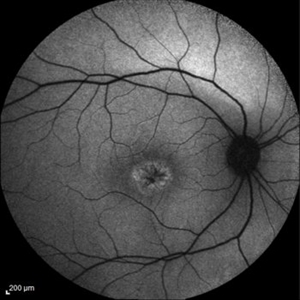

Late Stage Stargardt's Disease Late Stage Stargardt's DiseaseMar 13 2013 by Hamid Ahmadieh, MD Autofluorescence imaging of the right eye of a 46-year-old man with decreased VA due to advanced Stargardt's disease. Photographer: Nayereh Hadipoor, Negah Eye Center, Tehran Imaging device: Heidelberg Spectralis Condition/keywords: autofluorescence imaging, Stargardt disease

Late Stage Stargardt's Disease Late Stage Stargardt's DiseaseMar 13 2013 by Hamid Ahmadieh, MD Autofluorescence imaging of the left eye of a 46-year-old man with decreased VA due to advanced Stargardt's disease. Photographer: Nayereh Hadipoor, Negah Eye Center, Tehran Imaging device: Heidelberg Spectralis Condition/keywords: autofluorescence imaging, Stargardt disease